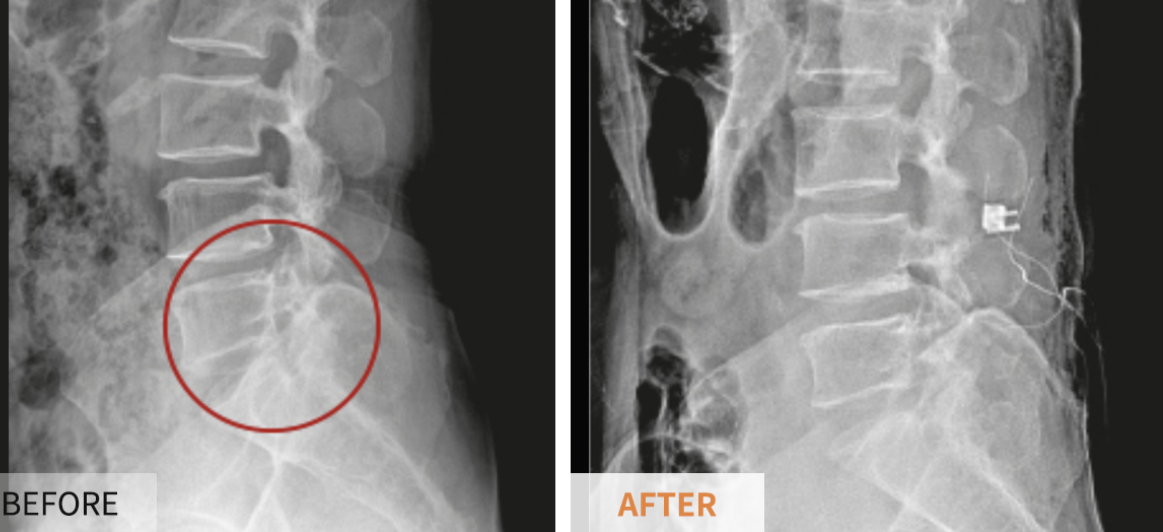

협착증의 진단은 환자가 호소하는 증상 등을 토대로 하여 신경학적 검사와 문진 등으로 척추관 협착증이 의심된다면 방사선학적 검사 상 확진해야 합니다. 다만, 단순 방사선 검사 상 척추 전방전위증(척추의 몸체가 아래 부분보다 앞으로 밀려나가 있는 것) 및 퇴행성 여부는 어느 정도 확인이 가능하나 척추관의 좁아진 정도를 확인하기 위해서는 척추 전산화 단층촬영, 척추 자기공명영상, 척수 조영술 등을 해야 합니다.

수술적치료의 경우엔 협착증이 가벼운 환자를 대상으로 신경성형술, 풍선확장술, 경막외신경차단술 등의 다양한 시술 치료를 시행할 수 있으나, 신경학적 이상소견이 있거나 협착증이 심한 환자는 효과가 미미하고 신경학적 합병증의 위험이 있으므로 전문의의 의견을 따르는 것이 좋습니다.